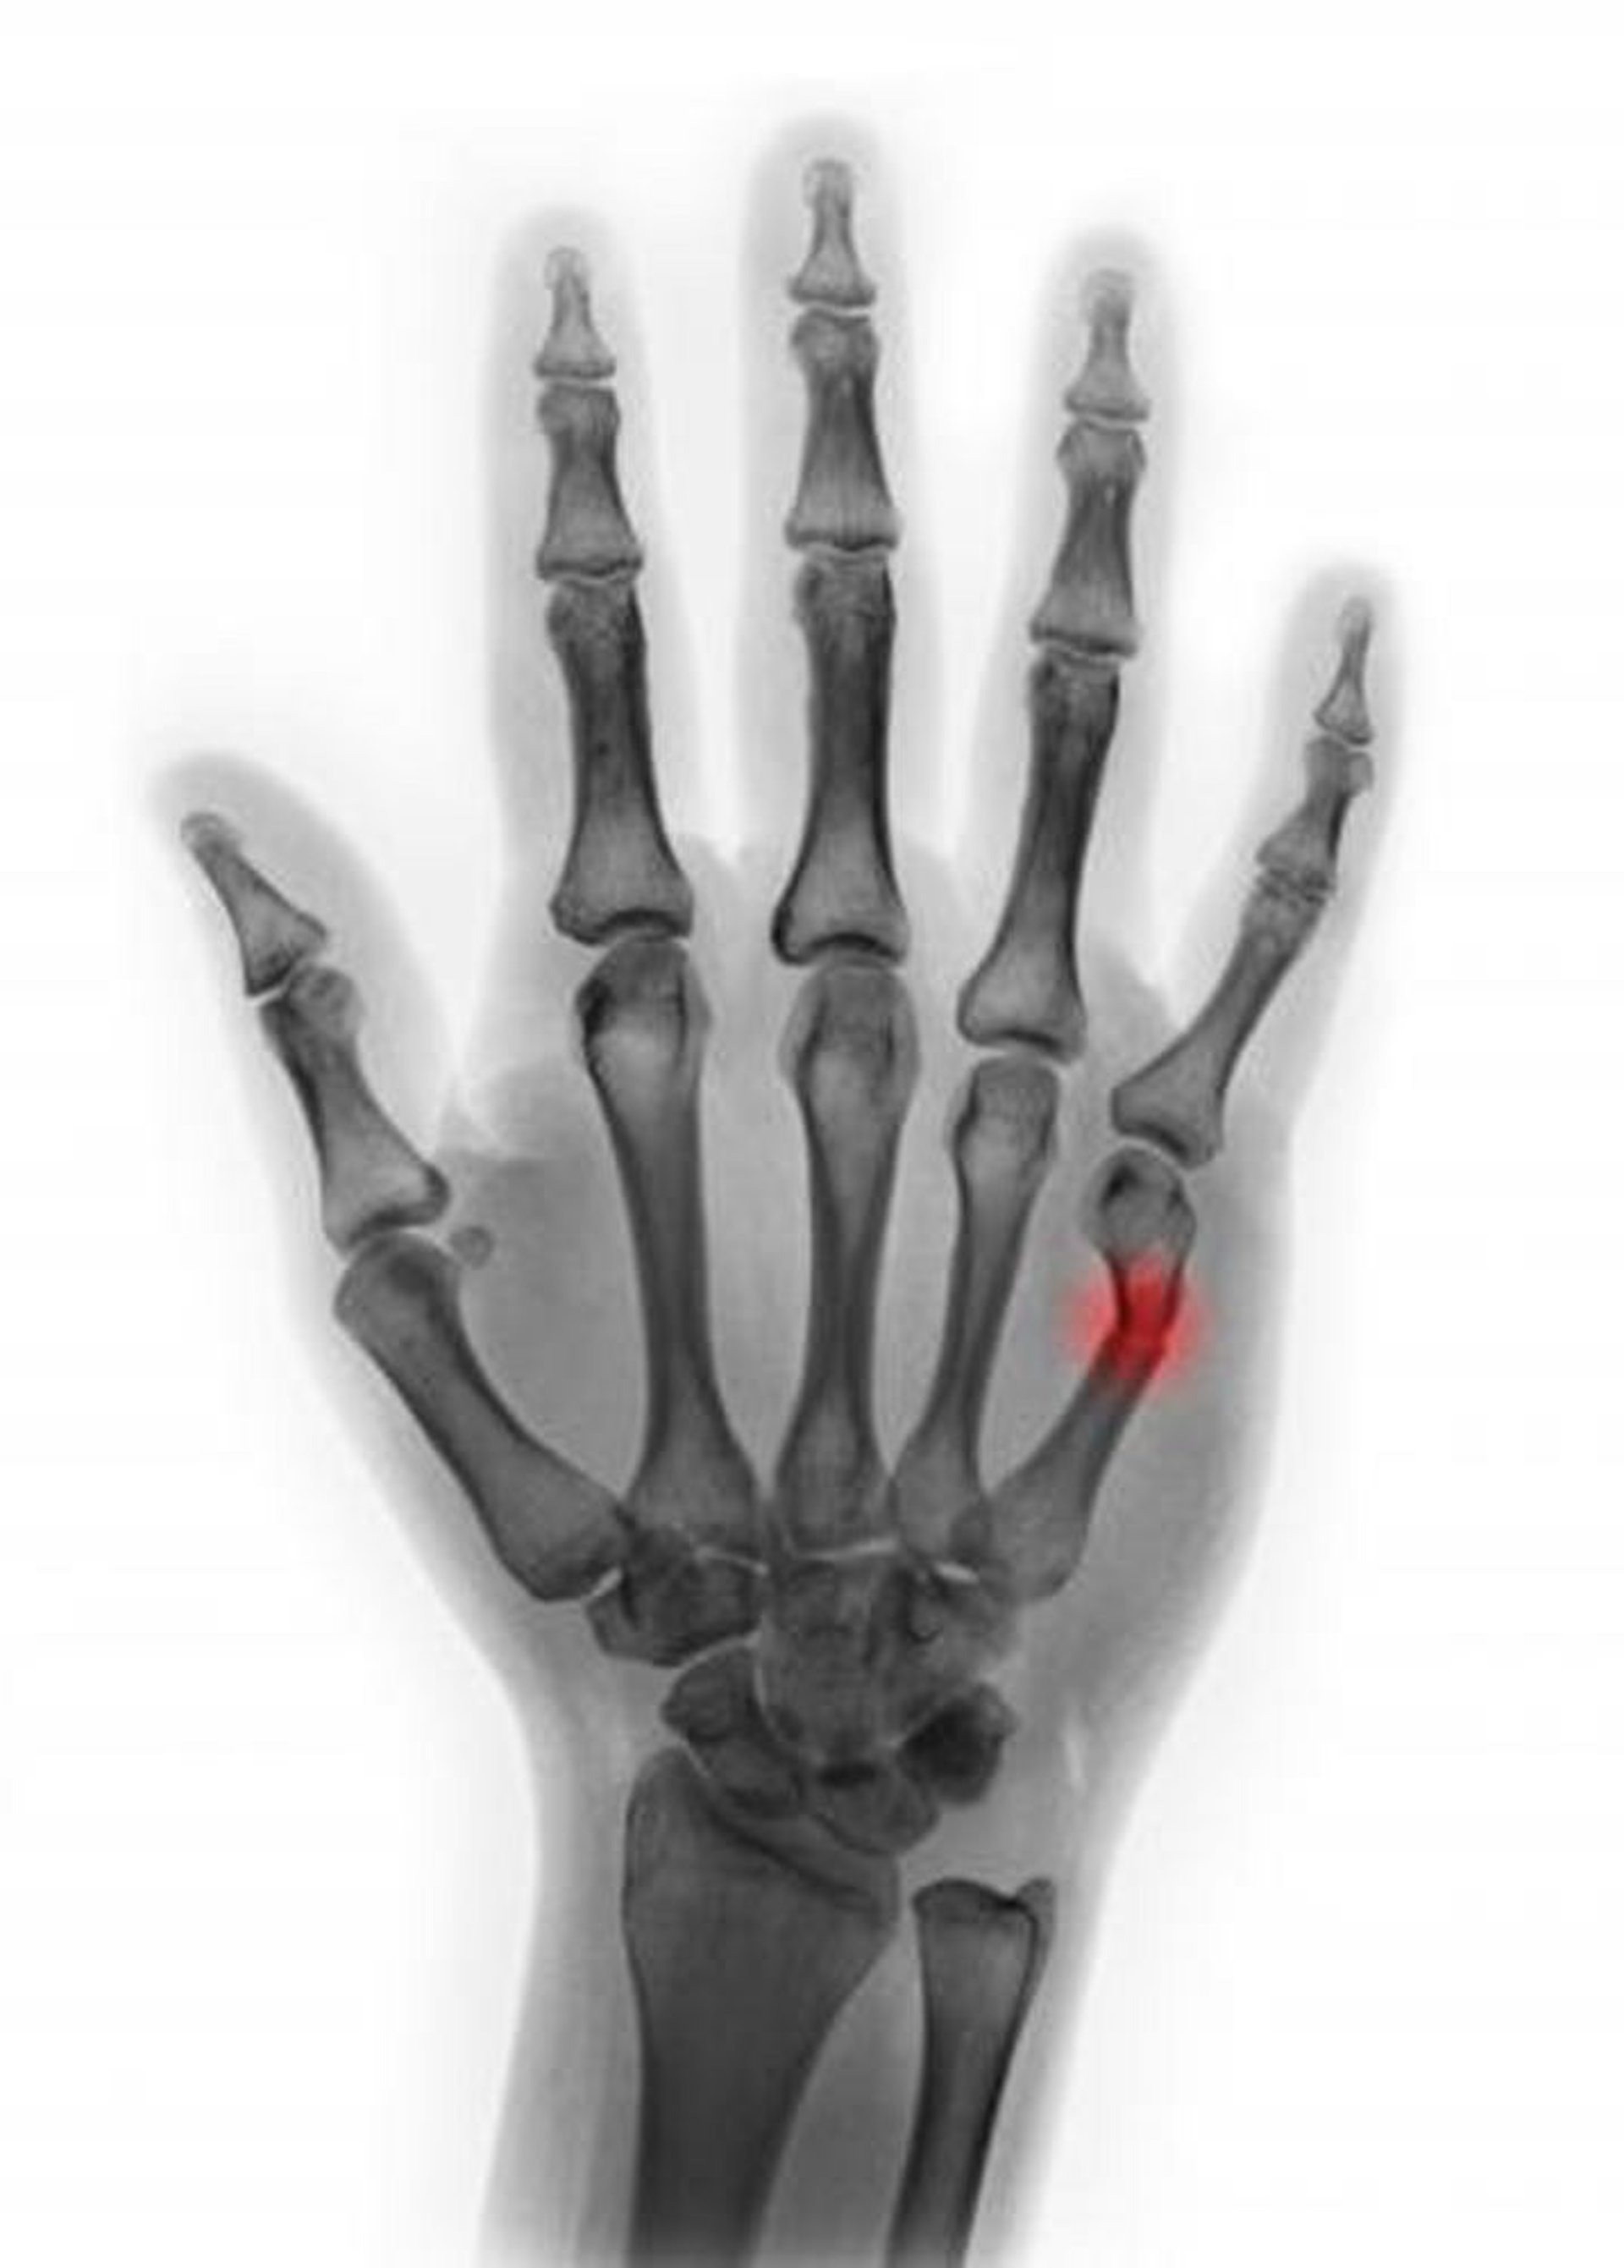

Перелом шейки пятой пястной кости

Этот цветной рентгеновский снимок показывает перелом шейки пятой пястной кости. На этом снимке, угол смещения <45°, который предполагает, что в репозиции нет необходимости.

SCOTT CAMAZINE/SCIENCE PHOTO LIBRARY